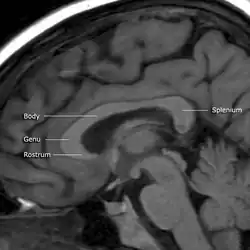

Das Corpus callosum besteht aus den Teilen Rostrum (Schnabel), Genu (Knie), Truncus (Stamm) und Splenium (Hinterende). Es verläuft auf dem Grund der großen Hirnlängsspalte und bildet das Dach der beiden Seitenventrikel.